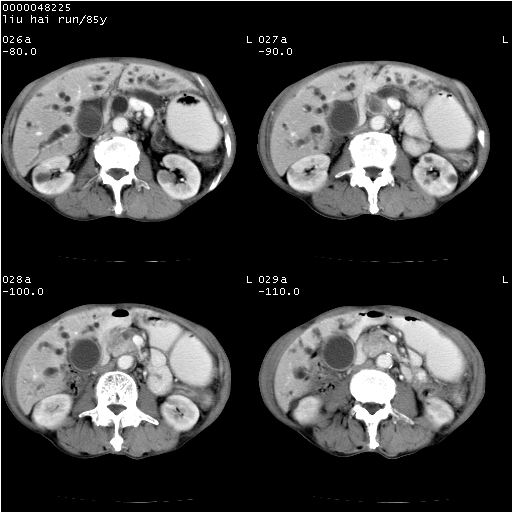

有“双管征”,胆总管胰头段突然中断,考虑为胰头癌。

影像表现:壶腹部扩张胆管呈截断样改变,肝内外胆管重度扩张,胆囊增大,胰管亦明显扩张,呈不规则患珠样,胰体尾部略有萎缩,增强扫描后壶腹部低密度影轻度强化,与钩突分界不清。

ct诊断:胆管癌。鉴别诊断:胰腺癌,胰腺癌为少血供肿瘤,增强后强化不明显,静脉期及延时后与正常胰腺分界清晰。

胆总管下端突然截断,胰腺萎缩,胰管扩张,肝内外胆管扩张,考虑胆总管下端癌可能性大。不除外胰腺钩突占位。

1)胆系低位梗阻(肝内外胆管扩张、胰管扩张、胆囊增大);考虑为:胰头癌可能性大,不排除胆总管下端癌。2)双肾多发囊肿。

胆总下端突然截断,肝内胆管呈软藤样扩张,支持胆管癌可能性大,建议mrcp.